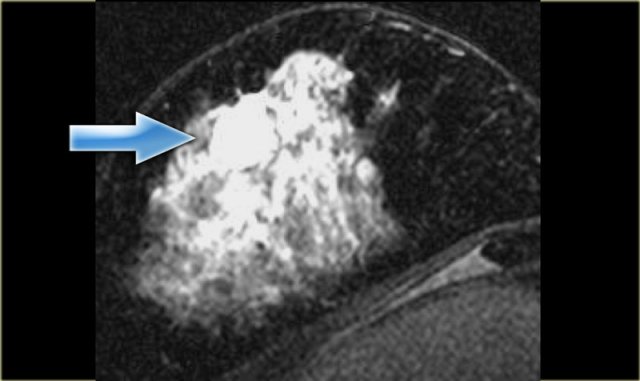

Margins can be described as smooth, irregular, or spiculated .

Spiculated margins are frequently a feature of malignant breast lesions and radial

scars.

If a mass has spiculated margins, it has an 80% chance of being malignant.

The image on the far left shows a spiculated mass, i.e. 80% chance of being malignant. .

Next to it the corresponding gross pathologic specimen.

You can see the spiculations invading the surrounding tissue in both.

Just like on mammography, this lesion is has a high likelihood of malignancy and would be labelled BIRADS 5.